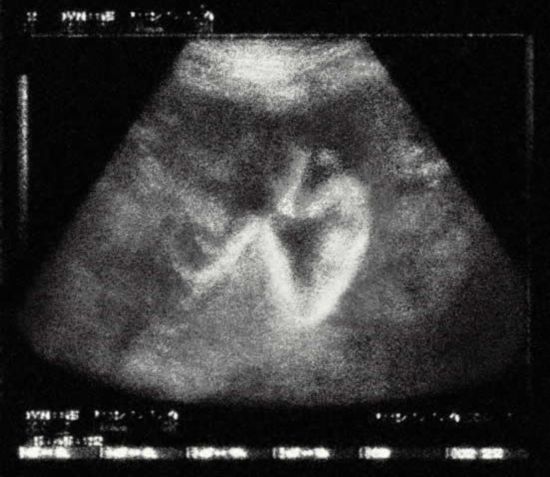

惊!胎儿竟会在体内哭泣

经有关部门证实,胎儿的啼哭声就像矿石收音机里的声音那样清晰。对于此类事,有人说是真,有人认为是假的。那么,胎儿究竟会不会啼哭呢?他们能否感受到母腹腔外喧闹世界的声音和暗示?